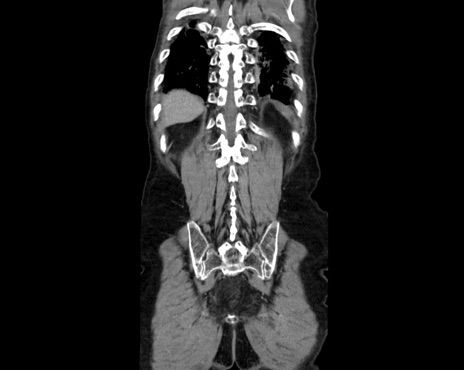

症例26(冠状断像)

【症例】80歳代男性

【主訴】嘔吐

【現病歴】昨晩2回嘔吐あり、今朝になっても嘔吐あり。来院。

【既往歴】胃潰瘍

【身体所見】意識清明、BT 37.6℃、BP 166/95mmHg、HR 100bpm、SpO2 97%、腹部:平坦・軟、腸蠕動音聴取良好、圧痛なし。

【データ】WBC 21900、CRP 1.4